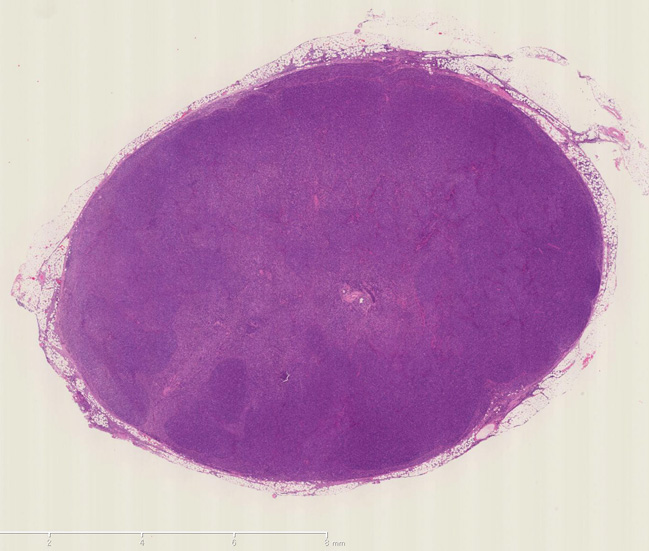

リンパ節はT細胞リンパ腫なので大きくない(12mmほど). びまん性に中-大型異型リンパ球がシート状密に増殖している。

腹膜リンパ節生検組織

病理組織診断: Adult T cell lymphoma---> 腹膜リンパ節の病理組織所見

ATL_HE01web.jpg 病理組織像のPDFファイルが見られます。

小型から中型リンパ球を背景にHodgkin cell, Mirror image cellなどHodgkin lymphoma, LPに似た組織像を呈する症例のようです. CD3, CD4がびまん性に陽性を示します.